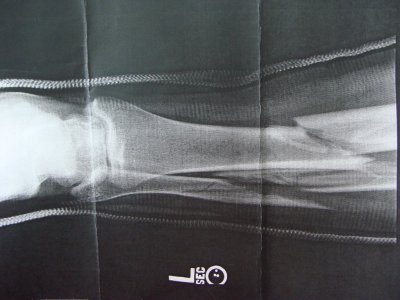

Этой зимой со мной произошёл неприятный случай при катании на лыжах - я получил перелом левой ноги. В травм пункте сделали рентген снимок, который показал тяжёлый перелом большой и малоберцовой костей левой ноги.

DSC01522.JPG